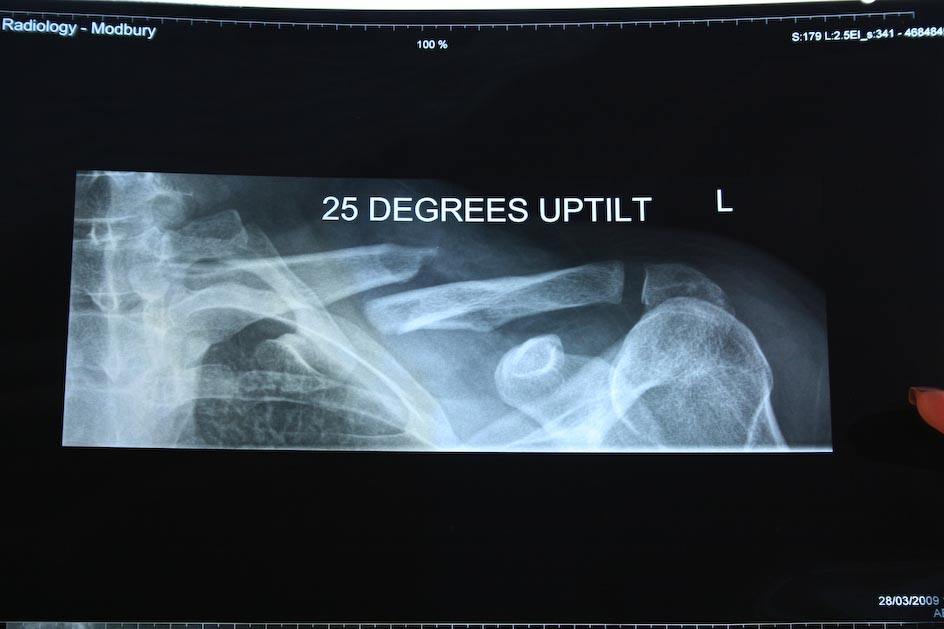

Snapped Collar Bone

Saturday 28Mar09